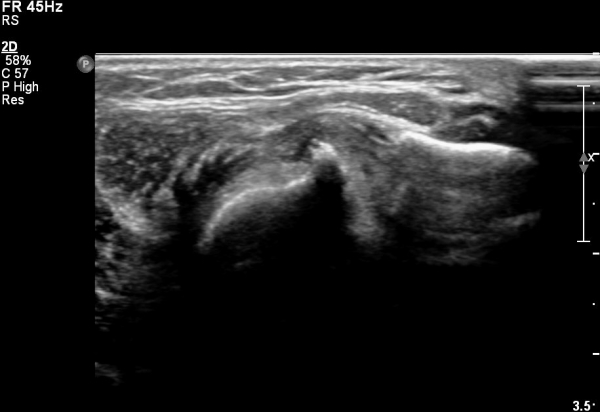

ÀÌµÎ¹Ú±Ù°Ç Á¾´Ü¸é°Ë»ç¿¡¼­ ¿ä°ñµ¹±âÀÇ µ¹Ãâ°ú °ñ±ØÀÌ °üÂûµÇ°í À̵θ·±Ù°ÇÀº Àú¿¡ÄÚ ºÎÁ¾°ú ¿¬°á ¼Ò½ÇÀÌ °üÂûµÊ(»çÁø 4, 5).